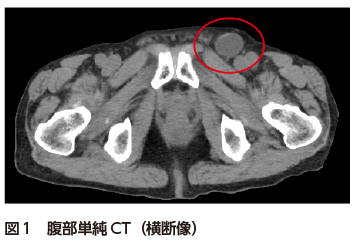

• A1:左鼠径部に小腸の脱出を認める(図12).また口側と思われる小腸および胃に拡張と内容物貯留を認める.骨盤内小腸には糞便様内容物(small bowel feces sign)を認める(掲載画像には非表示).

• A2:左大腿ヘルニアおよび小腸閉塞症.場所が類似する鼠径ヘルニアとの鑑別が重要(特に高齢女性の場合).

大腿輪は下腹壁動静脈の内側に位置しており,類似の箇所に位置する内側鼠径窩がヘルニア門となる内(直接)鼠径ヘルニアとの鑑別が重要である.男性の場合,腸管が鼠径管を通って陰嚢内へ脱出するか否かで鑑別は容易であるが,女性の場合はしばしば鑑別に苦慮する.鼠径ヘルニアはヘルニア嚢が鼠径靱帯の腹側(体表側)に,大腿ヘルニアは背側(深部側)に位置することが診断の手掛かりとなる.鼠径靱帯は横断像では同定が困難であるが,冠状断もしくは矢状断で多くの場合は同定可能であり,モニター上でスクロールしながら観察することで鼠径靱帯の同定,鼠径ヘルニアと大腿ヘルニアの鑑別がほぼ可能である4)

図2